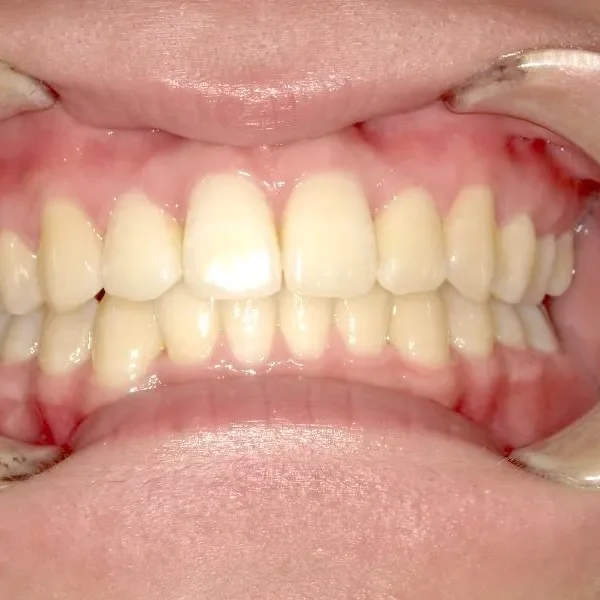

治療回数○回、2年9ヶ月の治療期間で矯正治療を終了しました。

主訴が改善され、ご満足頂きました。